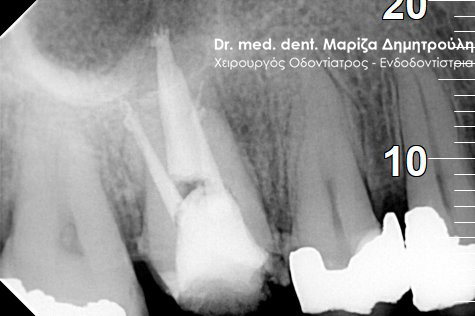

Root canal retreatment

BEFORE

BEFORE